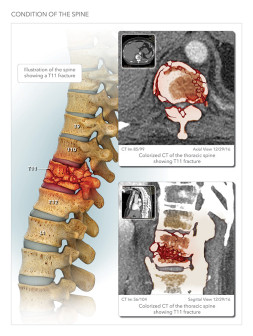

In the realm of legal disputes, the power of medical legal illustrations cannot be overstated, and to that end, MediVisuals + High Impact offers a variety of deliverables designed to help you connect with your audience and convey important facts of the case.

We create assets such as trial animations and illustrations that underscore the value of illustrations as medical trial exhibits:

Each of these legal illustrations is easily understood by diverse audiences, including both laypersons and respected legal professionals, and — perhaps more importantly — we have a track record of helping attorneys achieve favorable outcomes through the use of creative trial graphics and illustrations. Medical illustrations also serve as demonstrative evidence that can clarify and support expert testimony in legal cases. Additionally, custom visuals enhance patient education and compliance, and in medical malpractice cases they serve as powerful medical malpractice trial exhibits that support better informed consent and improved treatment adherence, helping attorneys overcome common medical malpractice case challenges with visuals.